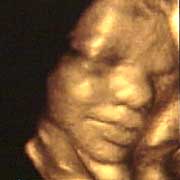

图文:胎儿子宫内表情丰富 专家称提供研究新依据

中新网9月13日电 英国天空新闻报道,英国科学家图亚特·坎贝尔最近利用先进的扫描技术清晰地拍下了孕妇子宫中胎儿的表情,透过他拍摄的照片,人们可以清楚的看到一个尚未降临世间的小生命喜、怒、哀、乐的表情。

斯图亚特.坎贝尔是伦敦著名的产科教授,他利用超声扫描技术拍摄到了胎儿在子宫中打呵欠、眨眼、吮手指、哭泣甚至微笑的画面,这些都为胎儿行为的研究提供了新的依据,专家认为,这一突破将推动婴儿健康科学的发展,包括对唐氏综合症等婴幼儿疾病的诊治将起到极大的推动作用。

此前,医学界一直认为,婴儿要到降生后才可以做出喜、怒、哀、乐的表情,要通过模仿母亲才可以学会微笑。

坎贝尔教授说:“有个这种技术,现在许多问题都可以进行研究了。比如说,患有唐氏综合症的婴儿和正常婴儿的活动方式是否一样?胎儿是否因为高兴才笑?胎儿哭是否是因为在子宫中受到打扰?既然我们都认为子宫内是一片黑暗,那胎儿为什么会眨眼呢?”(章田)